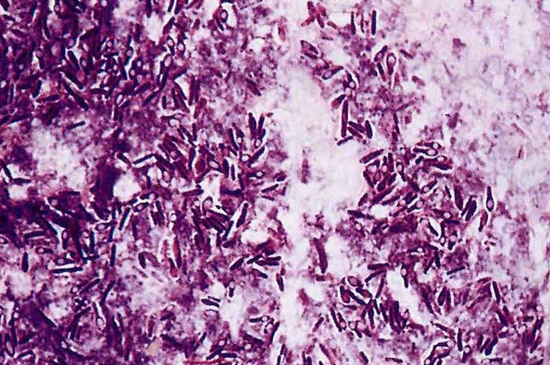

Клостридии представляют собой палочки, крупные, иногда слегка изогнутые, размером 4 — 22 х 1,4 — 2 мкм, подвижные, имеют до 25 жгутиков, располагаются часто цепочками. Возбудитель, как и все клостридии, являются облигатными анаэробами. Капсулу не образуют. Окрашиваются по Граму в фиолетовый цвет (грамположительные). Старые культуры утрачивают эту способность. Образуют овальной формы споры, располагающиеся центрально и субтерминально.

Рис. 14. Clostridium novyi. Крупные палочки, располагаются одиночно или цепочками.